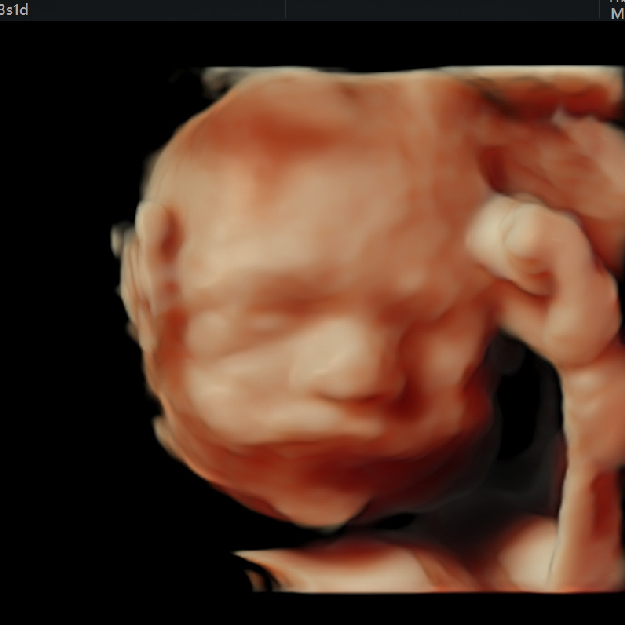

El ultrasonido es una técnica de diagnóstico por imagen; generada por de ondas de sonido que viajan a través de tu pancita, estas ondas de sonido son inofensivas para tu bebé, y nos permiten "fotografiar" y medir varias estructuras en formación.

8. Evaluación anatómica del feto después de las 11 semanas (preferentemente 12-14 semanas).